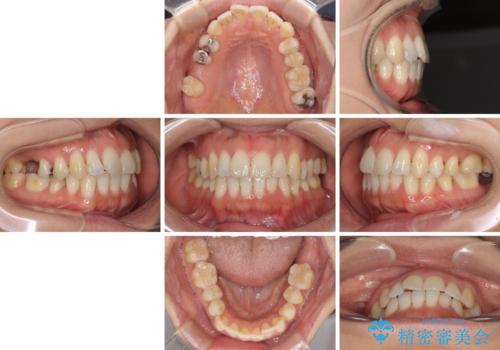

- 上下奥歯の欠損を気にして来院された患者様です。

以前矯正した後戻りにより前歯に叢生が認められたため、矯正治療の提案をしたところ、補綴治療と合わせて矯正治療を行うこととしました。

下顎欠損部はインプラントにて、上顎中間欠損部はブリッジによる補綴治療を行い、他にも気になっている銀歯をセラミックインレーやゴールドインレーにて修復治療を行うこととしました。

後戻りの程度は軽度であったため、インビザライン・ライトを用いて歯列を整えました。

再度後戻りするリスクを最小限に食い止めるため、下顎前歯の舌側を細いワイヤーで固定しました。